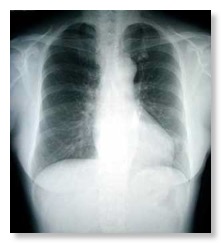

胸部腹部のレントゲン撮影が出来ます。 当クリニックでは、現像液を使わない・地球環境に優しいデジタル現像システム(KONICA MINOLTA Regius Sigma, Unitea-i)を導入しております。画像のデーターは汎用のデジタル画像(DICOM形式)で保存されるため、他の病院へ移動される際や紹介する際に、電子データーでお渡しする事が出来ます。(写真はイメージ図です。 後日写真をアップロードいたします)。 レントゲンシステムは島津メディカルシステム社のX’sy Pro SH systemを使用しています。 患者様の生殖器への被爆を少なくするため検査時にはプロテクターをはめて頂きます(少し重いです・・)。